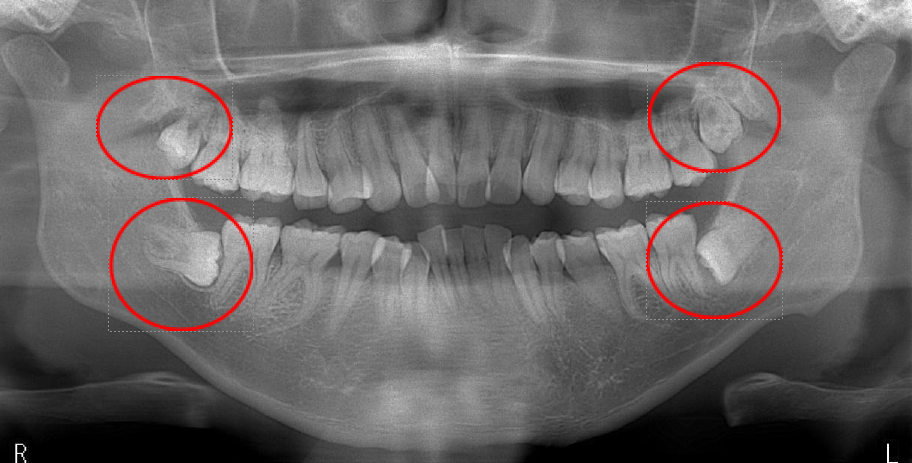

■ 神経を守るための「親知らずの抜歯 2回法(コロネクトミー)」にも対応

画像検査の結果、親知らずを一度にすべて抜歯すると、神経を傷つけて知覚鈍麻(しびれ)が起こる可能性が高いと判断される場合には、「2回法(コロネクトミー)」という方法を行うことがあります。

《方法》

① 1回目:親知らずの頭(歯冠)のみを除去

意図的に根の部分を残し、手術をいったん終了します。(保険診療)② 半年以上経過を待つ

歯ぐきの中に残った根が、時間とともに少しずつ前方へ移動し、神経から距離が離れていきます。→ そのため、神経損傷によるしびれのリスクを大幅に軽減できます。

③ 2回目:残っている根を抜歯

神経から安全な距離になった段階で根を抜歯します。(自費診療 27,500円)

神経との距離が非常に近い難症例でも、できる限り安全性を高める治療方法として選択できる点が特徴です。

※1回目の手術は保険診療ですが、2回目の手術は自費診療(27500円)になります。